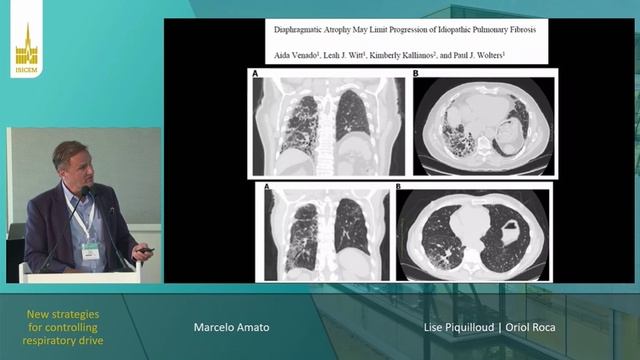

New strategies for controlling respiratory drive Marcelo Amato (ISICEM 2023)